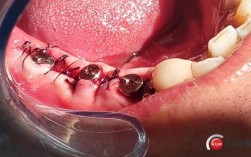

这是一种先进的种植牙技术,其核心特点是在拔除患牙后,立即(当天)在新鲜的拔牙窝内植入种植体,甚至有可能在植入种植体的当天或短期内(几天内)就安装上临时牙冠或修复体(即“即刻负重”)。

- 减少手术次数: 将两次手术(拔牙和种植)合并为一次,减少了患者的手术次数和创伤。

- 保存牙槽骨: 在拔牙后立即植入种植体,能有效防止拔牙窝周围的牙槽骨因缺乏功能性刺激而快速吸收和萎缩,更好地保留了骨量和骨形态,为最终修复提供更好的基础。